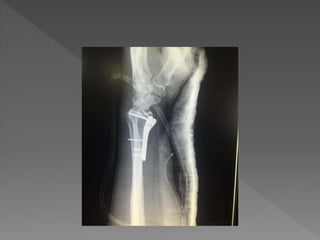

 Intra-articular fracture

 ORIF c LCP distal radius (VA) c locking

screw

 หลังผ่าตัดใส่ posterior long arm slab ในท่า supination

2-4 wks

 ORIF cLCP distal radius (VA) c locking screw

 หลังผ่าตัดใส่ posteriorlong arm slab ในท่า supination 2-4 wks